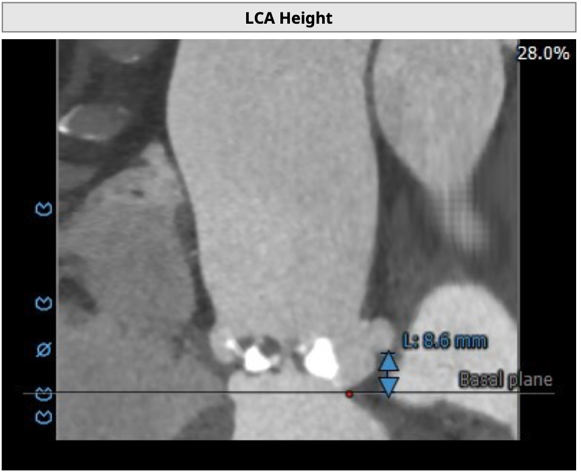

左冠开口高度8.6mm,右冠开口高度15.0mm,左冠高度偏低,左冠瓣瓣尖钙化明显,根据瓦氏窦内径和瓣叶长度综合判断,左冠存在较高堵塞风险;左心室后壁增厚。